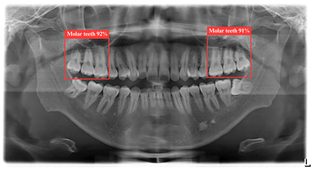

3.1. DPR Image Object Detection Result

Table 8 demonstrates a comparison of different YOLO model performances. First, YOLO11n has outstanding performance across all metrics in the ROI-I phase, achieving an accuracy of 90.0%. This represents a significant improvement compared to YOLOv8n (70.6%) and YOLOv10n (80.0%) while being slightly higher than YOLOv9n (89.5%). Its precision reached 94.4%, the highest among all models, indicating that YOLO11n effectively minimizes false positive results. The recall was also 94.4%, matching YOLOv9n’s performance. In molar teeth position detection, the image shows two highlighted regions with prediction accuracies of 92% and 91%, indicating consistent performance in molar teeth detection. In the ROI-II phase, YOLO11n achieved the best performance, with an accuracy of 93.2%, precision of 94.8%, and a remarkably high recall of 98.2%. For the single tooth position detection, the highlighted regions show prediction accuracies of 89% and 99%, demonstrating the model’s capability to precisely identify individual teeth. These metrics indicate that YOLO11n excels in classifying target regions and detecting all target instances. Additionally, its F1 score reached 98.2%, demonstrating exceptional capability in balancing precision and recall, further solidifying its advantage in detection and classification tasks.